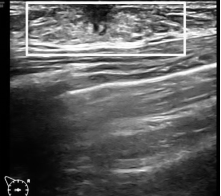

Tanner III期 腺体组织由乳晕后方向外延伸,中央为蜘蛛状低回声导管区

(白色方框)